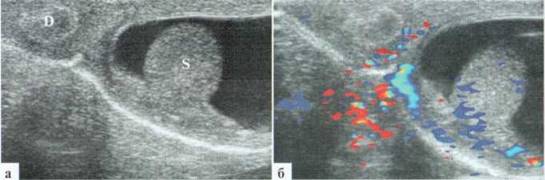

Извитость и/или атипичный ход сосудов семенного канатика при перекруте яичка наблюдается крайне редко. В некоторых случаях имеет место резко выраженный отек придатка и умеренное скопление жидкости в оболочках яичка. Размеры придатка могут практически достигать размеров яичка, контуры его выглядят неровными, структура — гетерогенная (рис. 2.6.2).

Рис. 6.2. Перекрут яичка и придатка у ребенка 12 лет: 1 — яичко; 2 — придаток